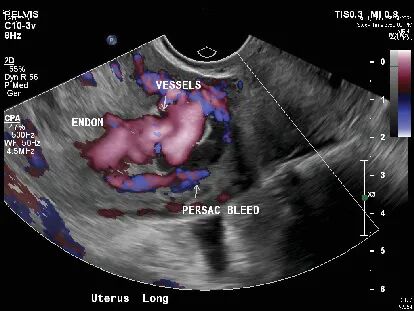

除此以外,超声探及子宫肌层右侧高度血管化区域,怀疑为子宫动静脉畸形,因为血流信号非常丰富,医生们决定必须查清楚。

流产后复查超声,结果报告显示血流信号不丰富,不像典型的子宫动静脉畸形,这与之前的CT血管造影和临床病史产生了矛盾。

宫腔镜下,医生看到了一个蓝紫色的血管团,凸向宫腔。

当宫腔压力降低时,它看得不清楚,这也解释了为什么怀孕时能发现,清宫后反而超声显示血流信号不丰富的原因了。

经阴道彩超是首选筛查工具,医生可以看到子宫里有一个富含血流信号的团块,多普勒技术能测到里面血流速度极快、阻力极低的特征,但本案例清宫手术后超声典型特征消失,可造成误诊。

这个案例特别强调了宫腔镜的价值,当超声等影像学检查结果不典型或自相矛盾时,宫腔镜能直接看到那个蓝紫色或暗红色的血管团凸向宫腔,从而一锤定音。